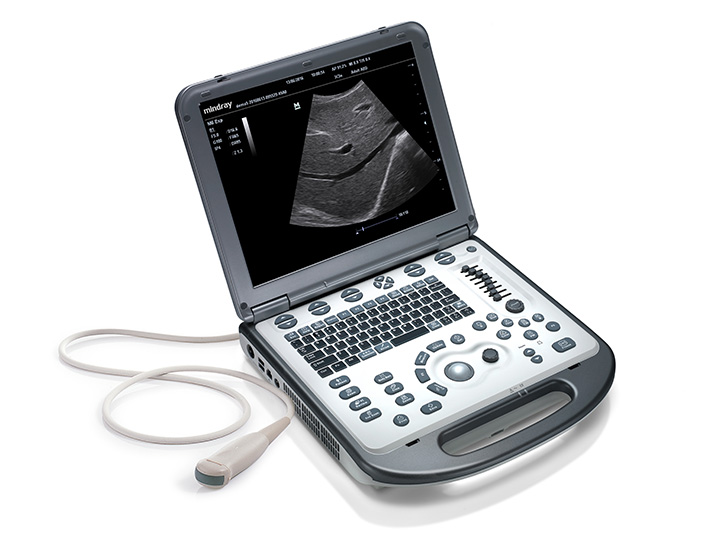

Veterinary Portable Ultrasound System

- Mindray Animal

- M6Vet

For modern veterinary clinics, what are the biggest challenges you need to face every day? How do you expand clinical capabilities to offer new services? How do you maximize the utilization of your ultrasound scanner to increase the throughput? How do you satisfy the needs of patients and referrers to differentiate your clinics from others?

If the issues above are your concern, then Mindray’s hand-carried ultrasound system M6Vet is the answer. With 3T Transducer Technology™, a comprehensive veterinary share service and reproduction package, and one push button iTouch™ image optimization technology, M6Vet enables your daily success for routine veterinary exams.

Ergonomics

-Lightweight Hand-carried design

-Specially designed cart with built-in handle

-1TB high hard drive capacity

-Up to 90 min uninterrupted scanning with rechargeable battery